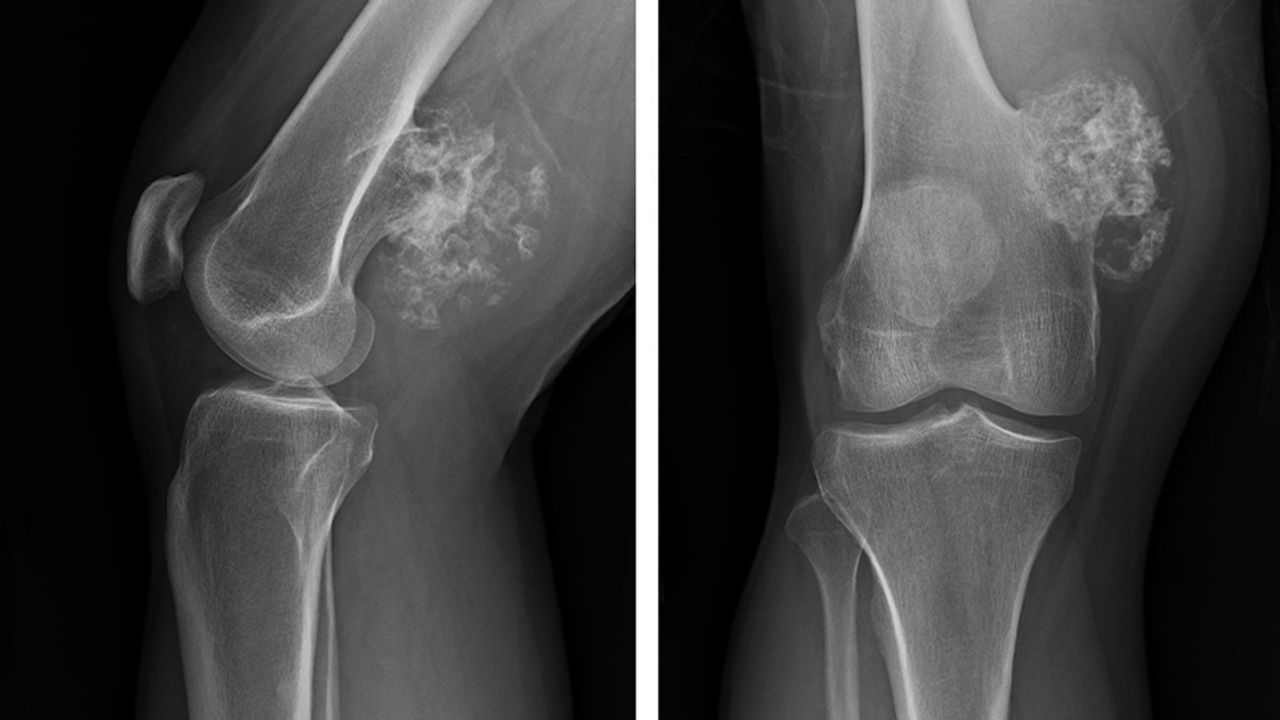

İyi huylu kemik tümörleri genellikle yavaş ilerliyor ve eklem ya da kemikte ağrı, hareket kısıtlılığı ve aksama gibi şikâyetlerle ortaya çıkabiliyor. Bu tümörlerin bir kısmı düzenli takiple kontrol altında tutulabilirken, kırık riski veya hızlı büyüme potansiyeli olanlar cerrahi müdahaleyle temizlenebiliyor. Kötü huylu kemik kanserlerinde ise şiddetli ve giderek artan kemik ağrısı, tümöre bağlı kırıklar ve şişlik gibi belirtiler öne çıkıyor.

Kemik ve yumuşak doku tümörlerinin teşhisi radyolojik tetkikler (grafi, MR, tomografi, PET-CT) ile konuluyor. Geniş cerrahi operasyonların ardından protez, plak-vida ve çiviler kullanılarak kemik sağlamlaştırılıyor. Osteosarkom ve Ewing sarkom gibi bazı kötü huylu tümörler özellikle çocukluk ve ergenlik döneminde acil tedavi gerektiriyor.

Erken tanı ve modern cerrahi teknikler sayesinde geçmişte yüzde 40’lara varan amputasyon oranları günümüzde yüzde 3-4 seviyelerine kadar düşmüş durumda. Bu da hastaların uzuv kaybı yaşamadan tedavi edilebilmesine imkân tanıyor.